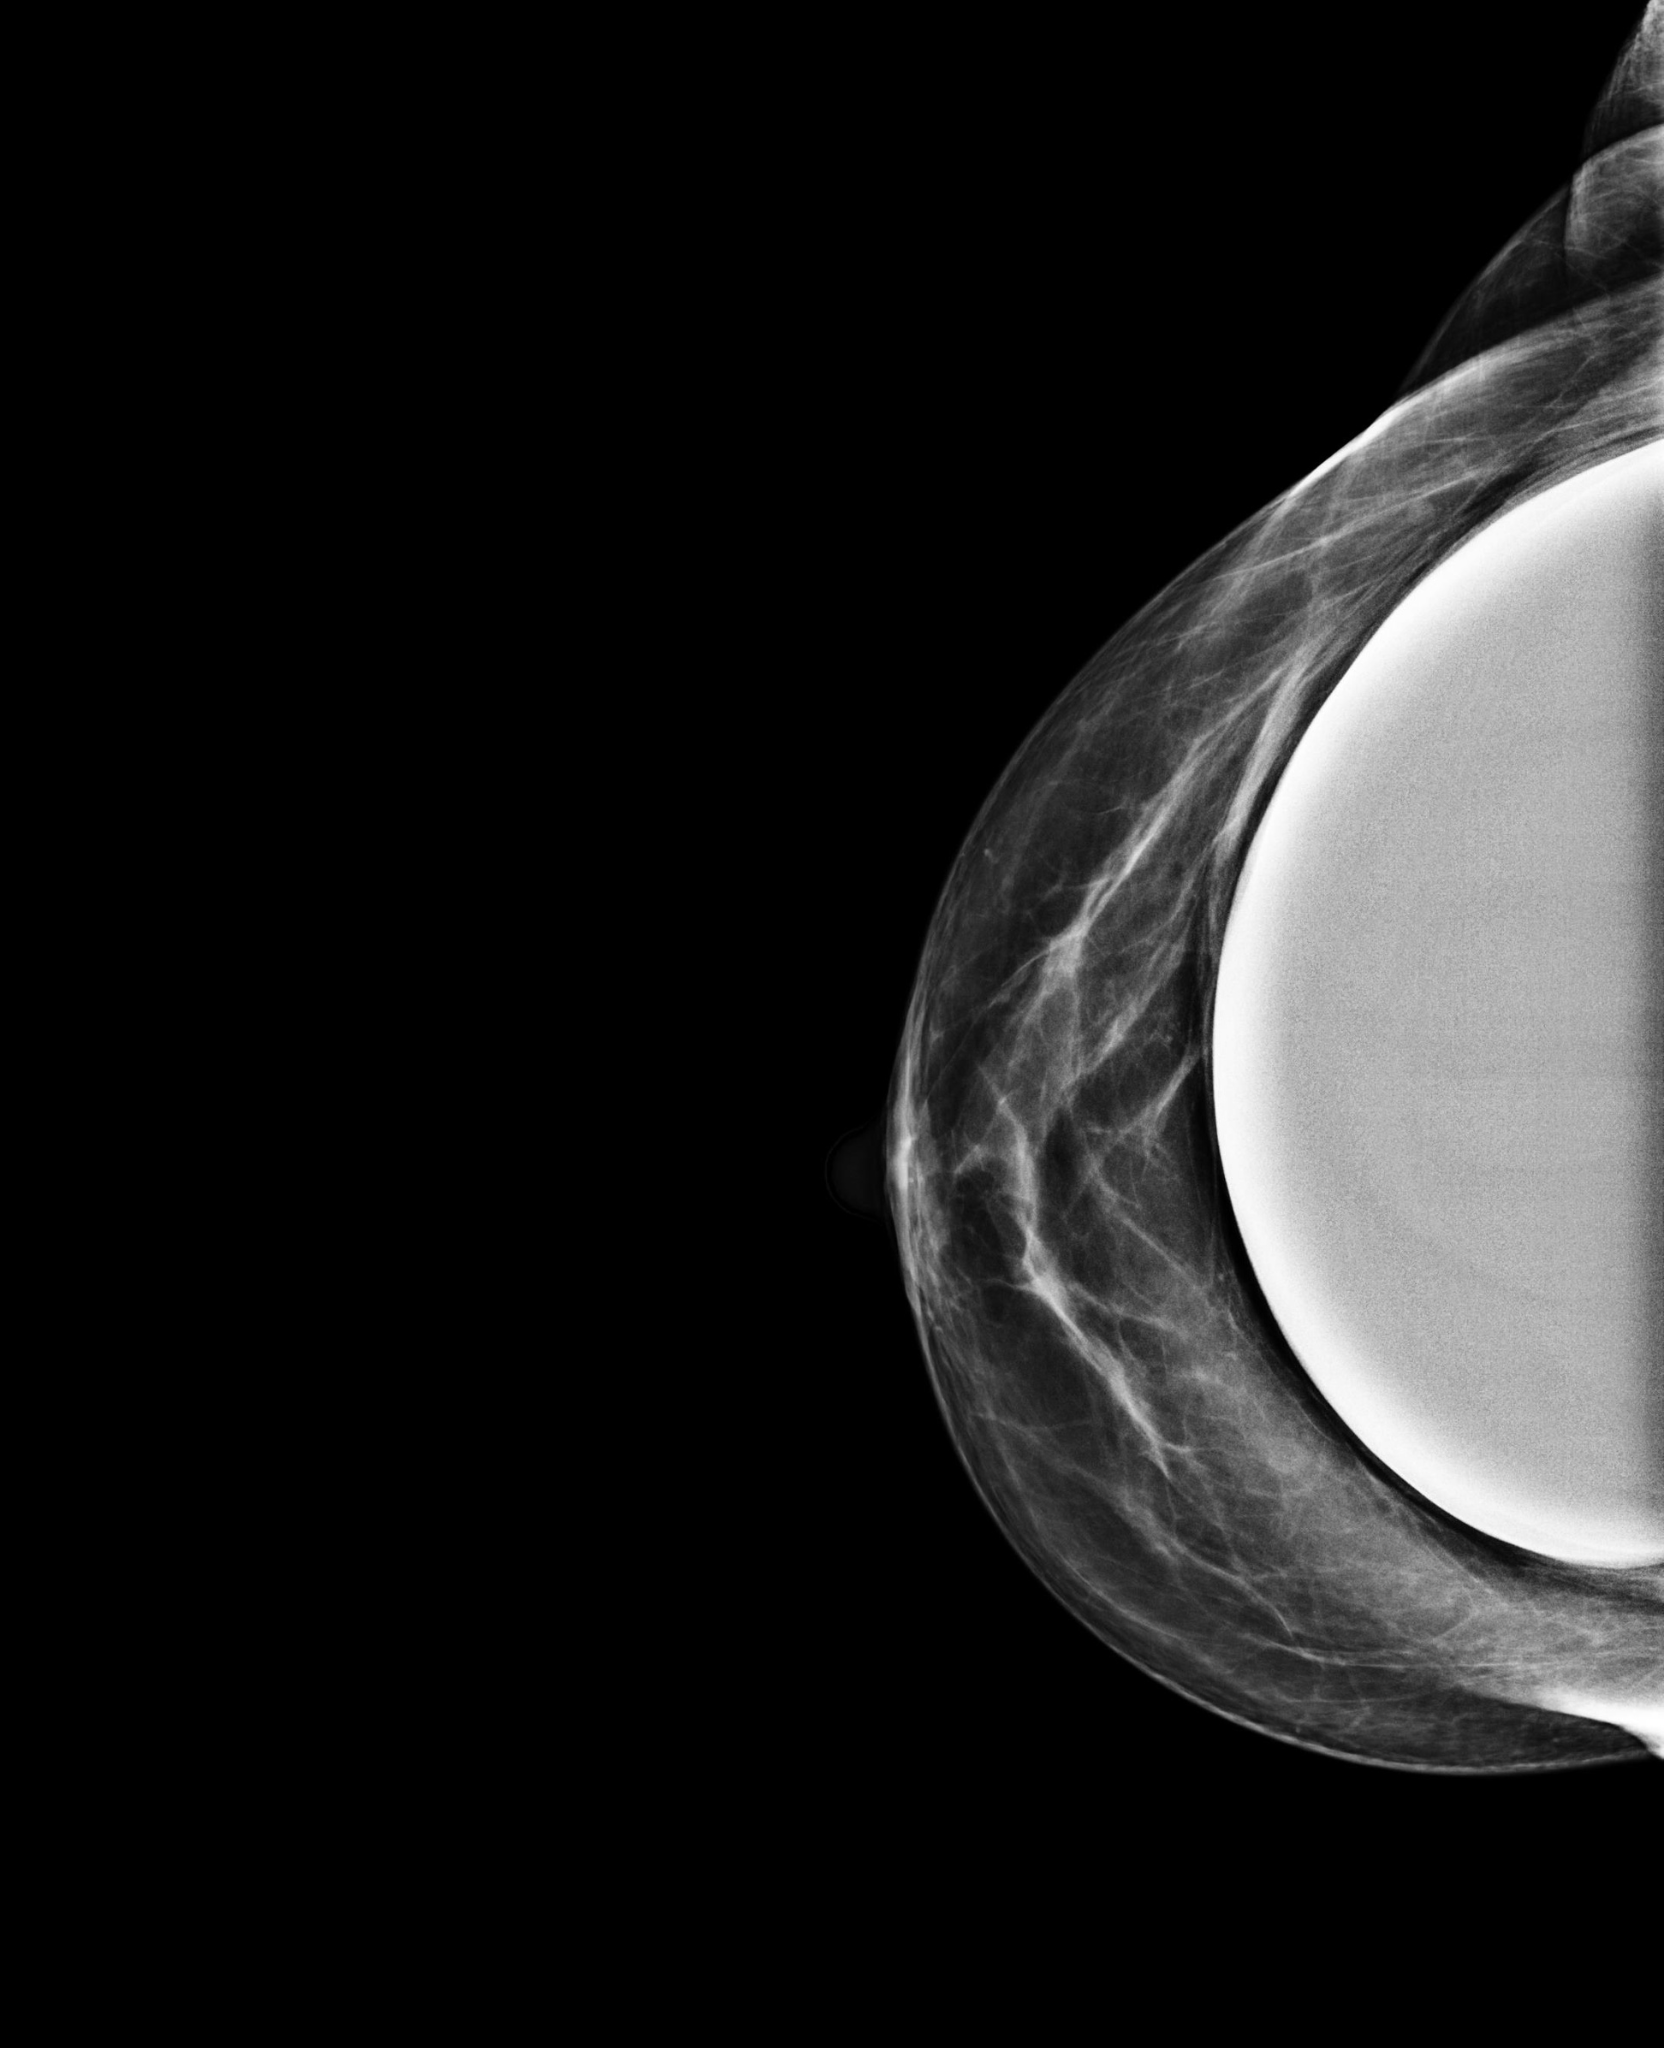

BreastScreen NSW radiographers are trained in taking mammograms for women with breast implants. The pictures below show how special techniques are used to image the breast tissue around implants.